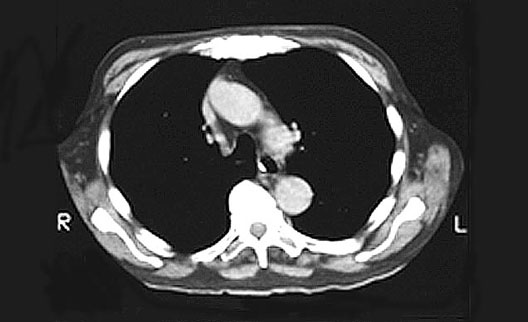

Heart CT

1. Ascending aorta

2. Descending aorta

3. Trachea